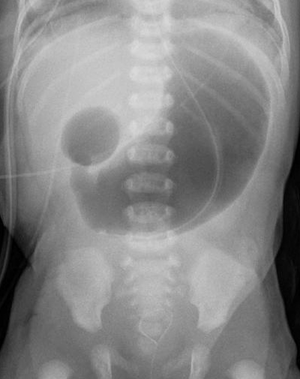

diagnosis of duodenal atresia?

abdo x ray : double bubble sign

ie. distension of stomach and proximal duodenum w absence of gas throughout the rest of the bowel